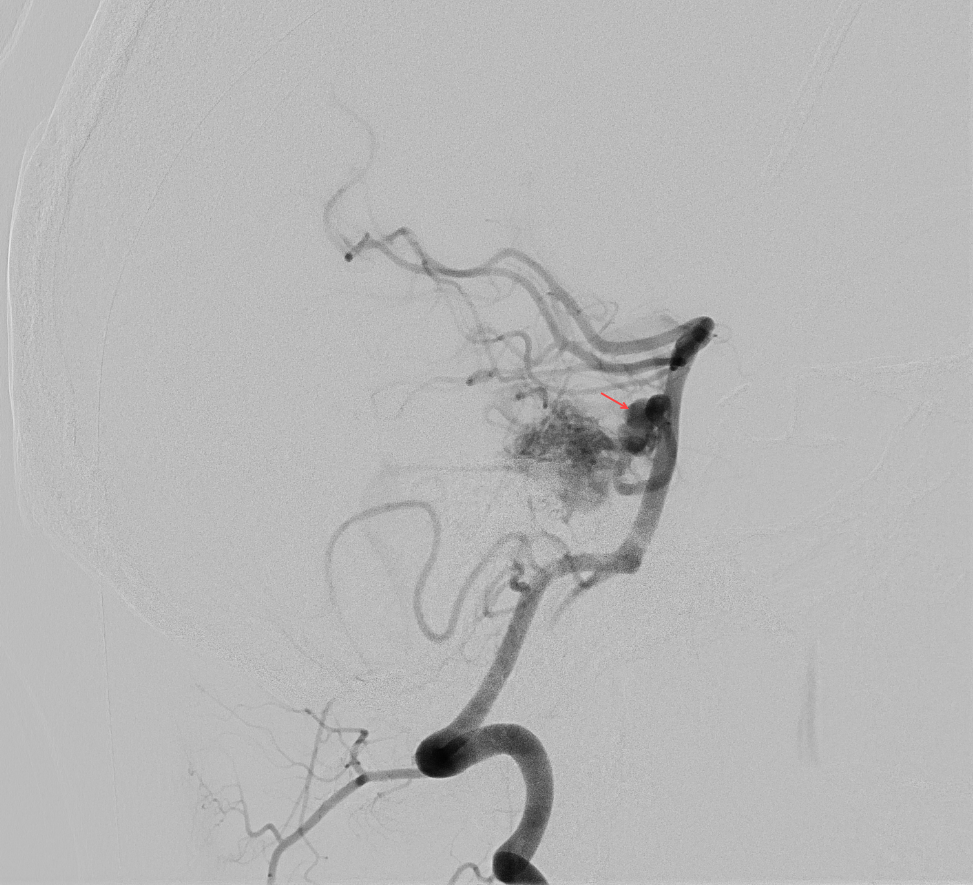

Intranidales Aneurysma

Unter einem intranidalem Aneurysma versteht man ein Aneurysma, welches sich im Nidus einer AVM befindet. Das vorhandensein eines intranidalen Aneurysma erhöht das Blutungsrisiko einer AVM[^1].

Der Goldstandard in der Beurteilung einer AVM und einem damit assoziierten intranidalen Aneurysmas ist die digitale Subtraktionsangiographie (DSA). Charakteristischerweise füllt sich ein intranidales Aneurysma früh in der DSA[^1].

- Angiographie einer Arteriovenöse Malformation mit einem assoziierten intranidalen Aneurysma.